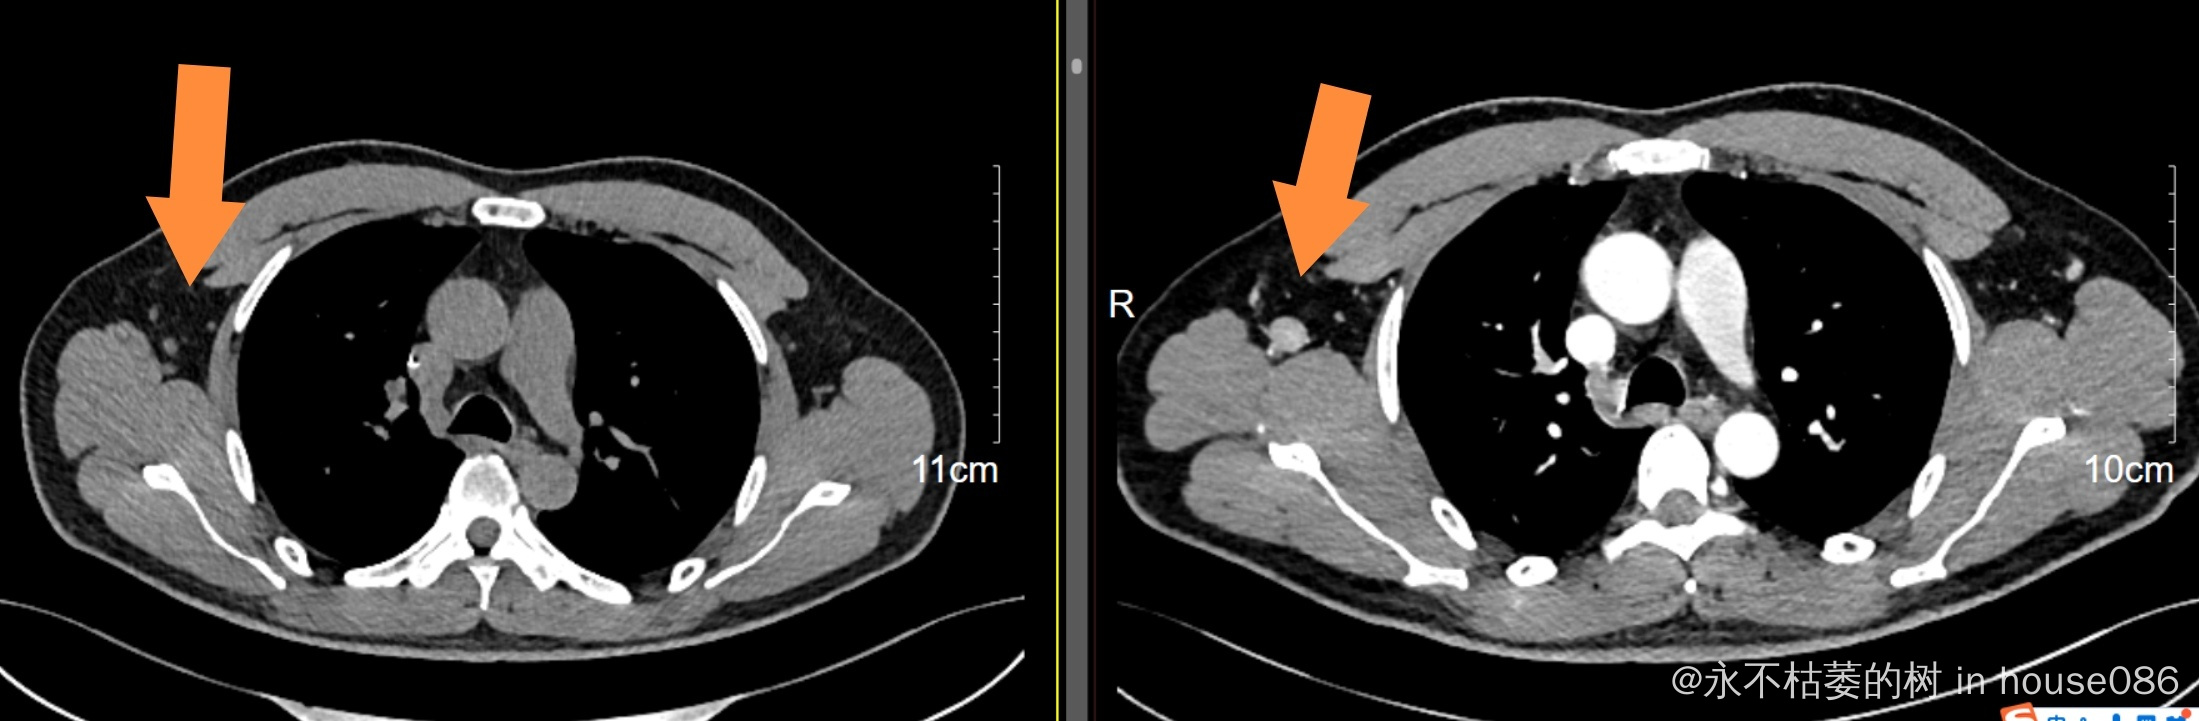

目前2周期化疗后第14天查白细胞低了,中性粒细胞0.6*10*9,打了两次短效升白针(隔天一次),第18天查恢复了,只是睡眠很差,常需要助眠药辅助睡眠,今日今日复查了颈胸腹部CT,大多数病灶都缩小了大概50-70%不等,我还是很欣慰,我是准备4周期后再做PETCT行中期评估。